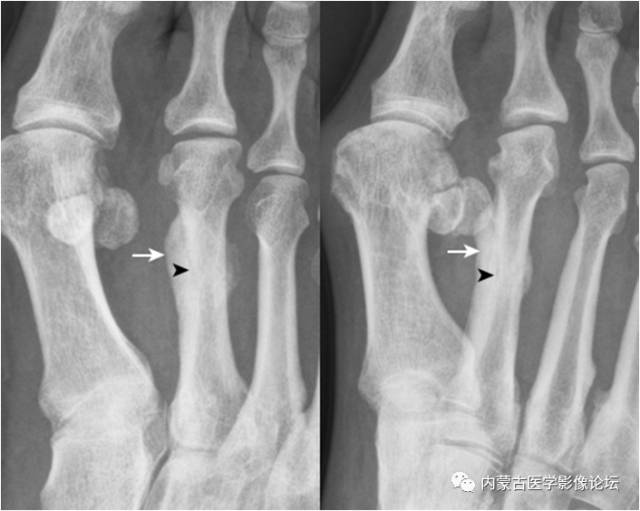

19.拇趾多分籽骨:拇趾内外侧籽骨可表现为二分籽骨(箭)或三分籽骨(箭头),为正常变异,需与籽骨骨折、坏死鉴别。骨折边缘多不规则,坏死密度多不均。